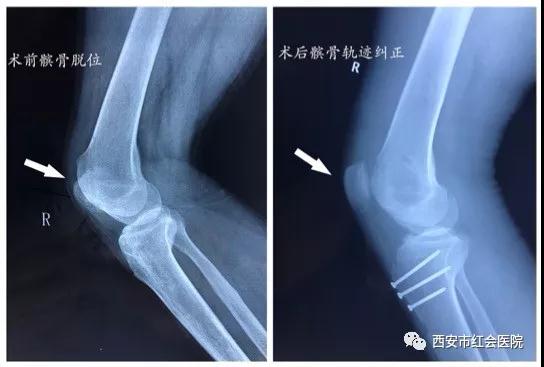

近日张宪副主任带领手术团队为患者进行了习惯性髌骨脱位3D打印辅助综合矫形手术,顺利完成髌骨外侧松解、胫骨结节截骨移位(Elimslie-Trillat技术)、内侧髌股韧带重建(MPFLR)及滑车成型术(Deepening Trochleoplasty)综合矫形手术,术后患者髌骨外脱位轨迹纠正,目前患者已经可以自行下地行走并开始康复训练,手术效果满意。